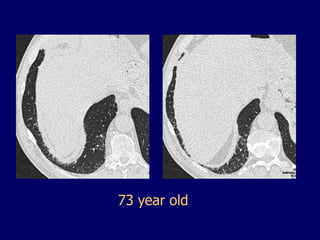

73 year old

• Cigarette smoking •Ageing (presbyteric) lung “expected” changes